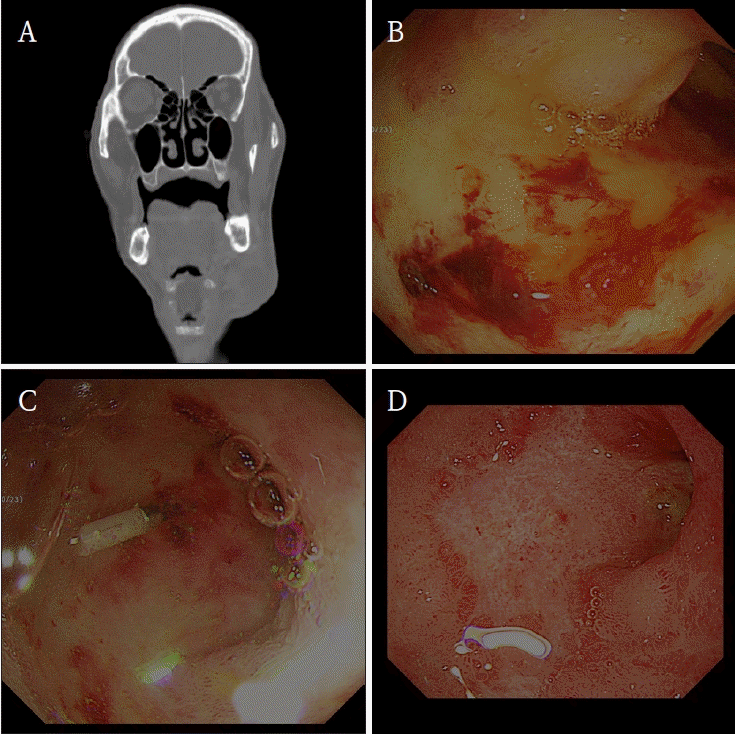

An 80-year-old man was admitted to emergency center, with complaints of swelling and pain in the left cheek. Initial laboratory tests showed a red blood cell (RBC) count of 2.37 × 10⁶ /μL and a hemoglobin (Hb) level of 7.9 g/dL. Computed tomography (CT) showed an abscess in the left submandibular region (Fig. 1A). An extraoral surgical drainage was performed, and the patient was admitted for supportive care.On the third day of admission, follow-up laboratory tests showed decrease in RBC count (1.99 × 10⁶ /μL) and Hb level (6.6 g/dL). The blood transfusion was performed. Despite the transfusion, by the sixth day of admission, RBC counts (2.25 × 10⁶ /μL) and Hb levels (7.3 g/dL) remained low. Since no active bleeding was observed at the surgical site, an anemia work-up was made, including stool occult blood test.On the eighth day of admission, the patient showed hematemesis. His blood pressure decreased to 88/59 mmHg. Fluid resuscitation was initiated. Laboratory tests showed Hb level of 5.6 g/dL, requiring additional transfusion. The result of stool occult blood test was positive, indicating gastrointestinal hemorrhage. A medication history found that the patient had been taking unspecified liquid painkiller daily for two weeks (approximately 2 boxes) before admission. He had also taken naproxen (Anafje Soft Cap 250 mg, Yuyu Inc., Seoul, Korea) and acetaminophen (Geworin Tab 300 mg, Samjin Pharm, Seoul, Korea).A mucosal ulceration with adherent blood clots was observed in emergency upper gastrointestinal endoscopy. After the clot removal, oozing vessels was exposed (Fig. 1B). Hemostasis was achieved through epinephrine injection and cauterization (Fig. 1C). Continuous PPI therapy with 2 vials of esomeprazole (OMPS injection 40 mg, Chong Kun Dang Pharmaceutical Corp., Seoul, Korea) mixed in 100 mL of normal saline was initiated, and the patient was kept nil per os (NPO). On the thirteenth day of admission, as the patient’s condition stabilized, he was discharged from the hospital (Fig. 1D).- Case 2

Figure 1.

A. Computed tomography shows an abscess formation on left submandibular area. B. Endoscopy shows an active bleeding on upper gastric area. C. Bleeding sites are managed by electrocauterization. D. Follow-up Endoscopy shows no signs of active bleeding.